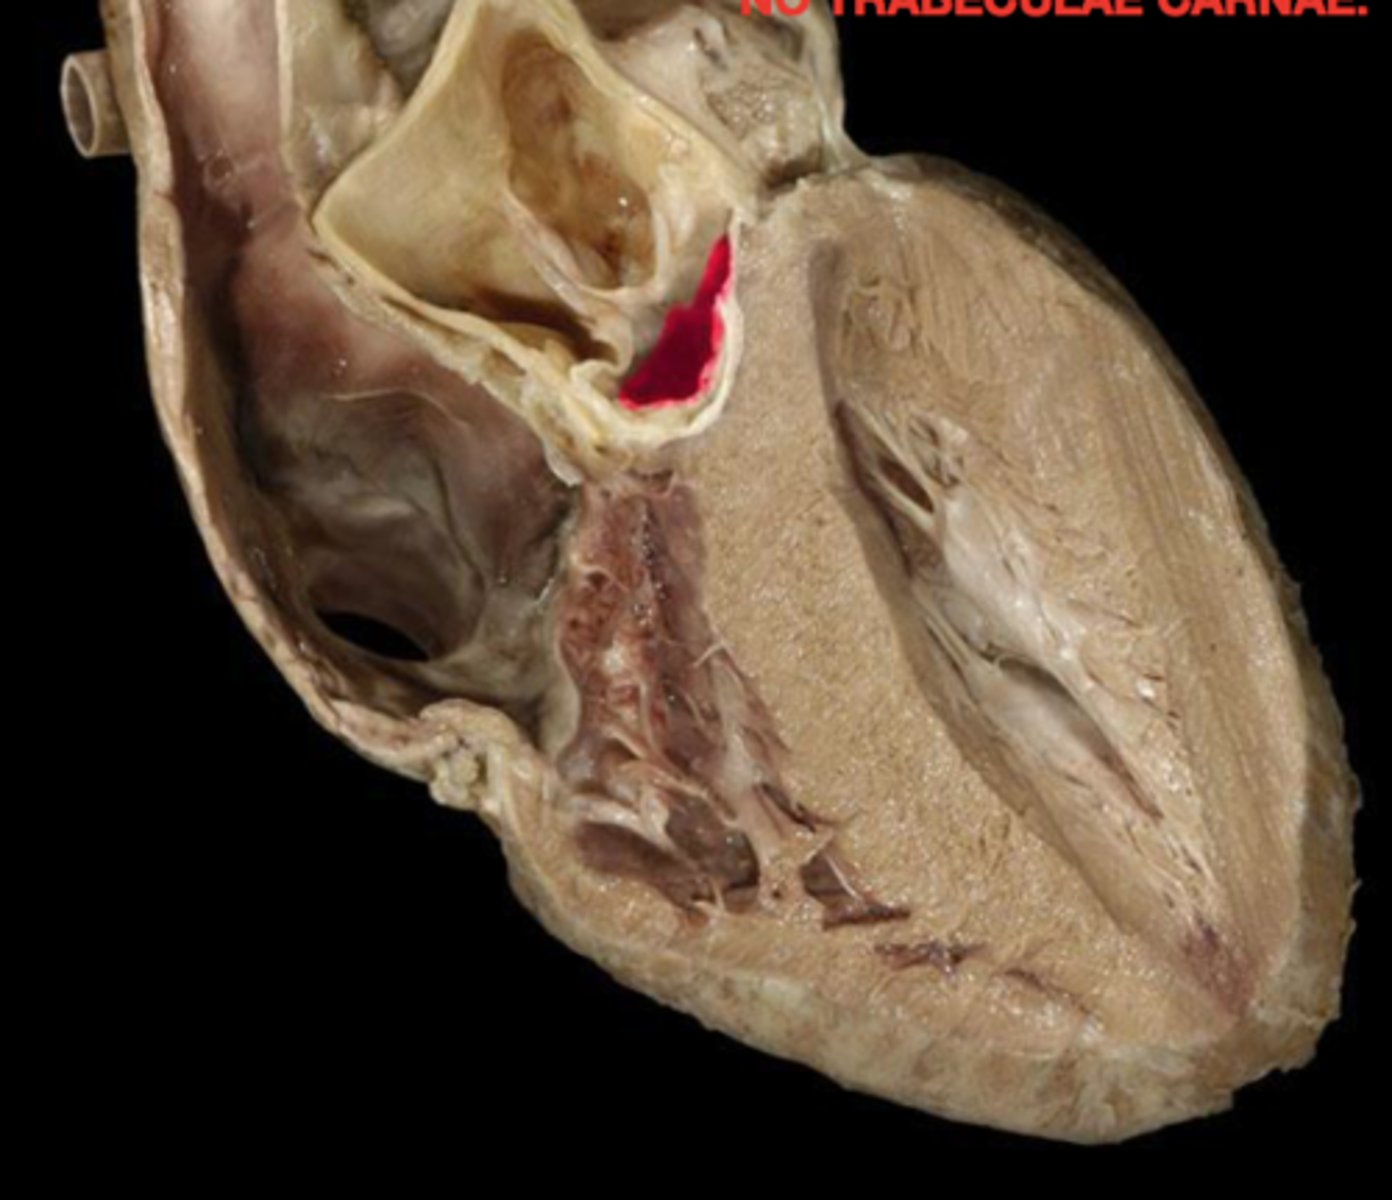

trabeculae carneae

ridges of cardiac muscle